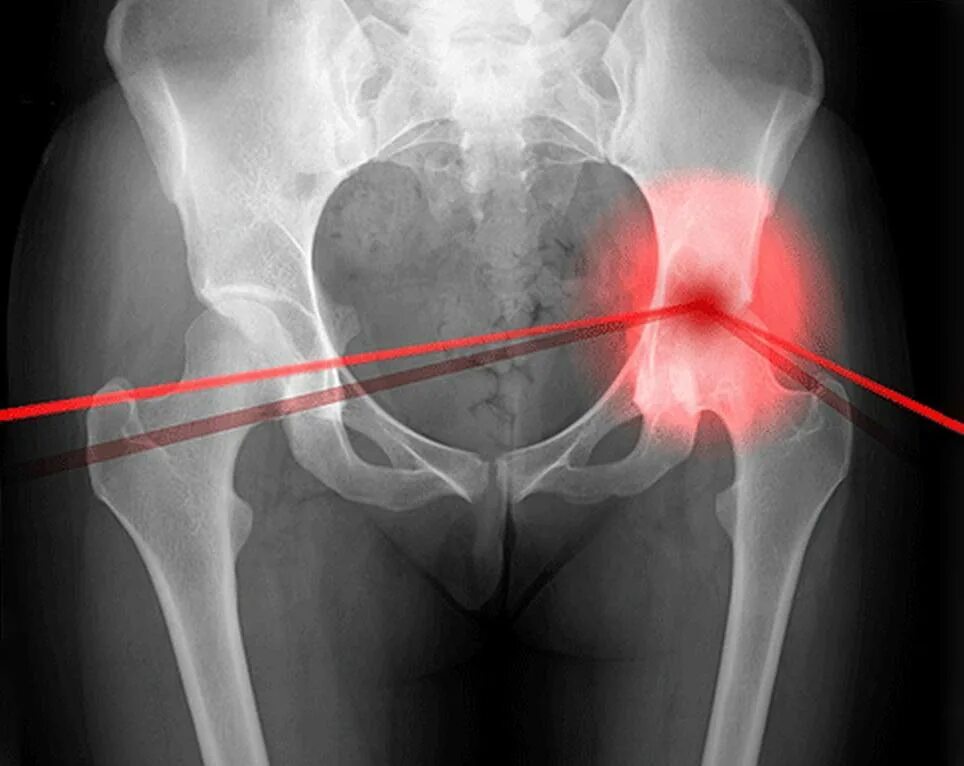

Щель тазобедренного сустава